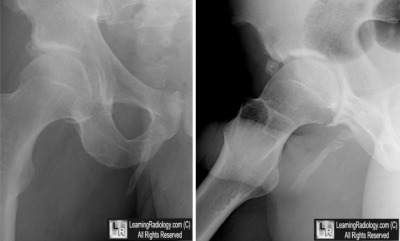

• 32 year-old with hip pain after fall

AP and lateral view of right hip

3. Pelvic Digit

Pelvic Digit

• Rare congenital anomaly

• Bone develops in soft tissue

• Can arise from any of the pelvic bones; also anterior abdominal wall

• Most commonly arises from ilium

• Unilateral

• Believed to arise in mesenchymal stage of bone growth within first 6 weeks of embryogenesis